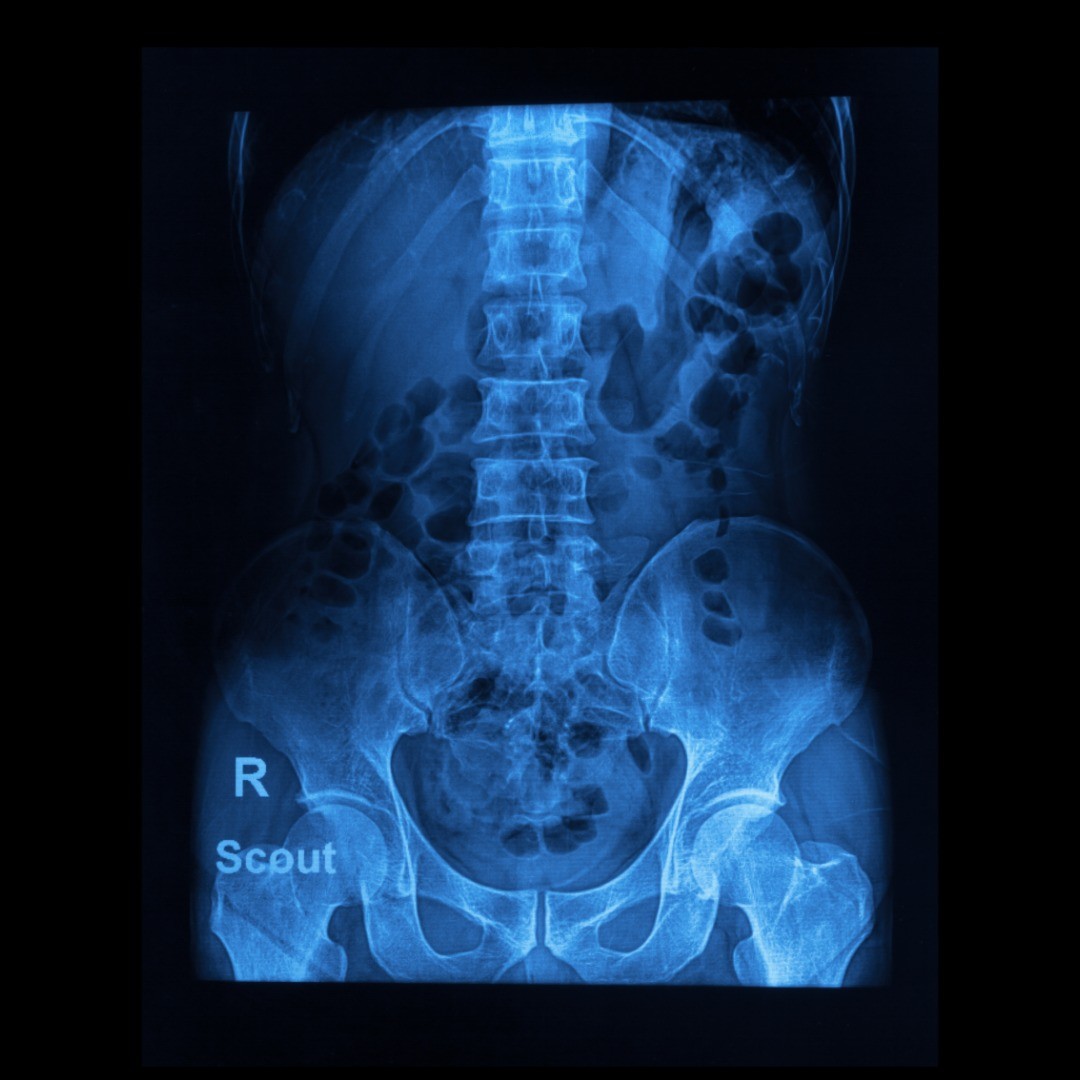

Kyphoplasty is a minimally invasive spine procedure that provides fast pain relief and lifts the fractured vertebral body of the spine; it is used to treat spinal compression factors. Compared to traditional surgery, this procedure uses a smaller incision with fewer complication risks and a faster recovery time.

Kyphoplasty treats unhealed spinal compression fractures that are causing debilitation and chronic back pain.

Osteoporotic spinal compression fractures are especially common in those over the age of 70. Although most candidates for kyphoplasty have vertebral breaks due to osteoporosis, compression fractures can also occur due to cancer or trauma.